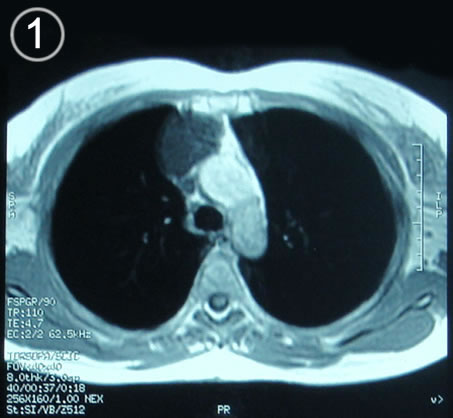

Corte Axial en secuencia T1

Corte mediastinico aortico a la altura del cayado.

a: lesión redondeada por delante de aorta ascendente en su arco, de aspecto homogéneo bien limitada.

b: El cayado aortico.  t: la traquea